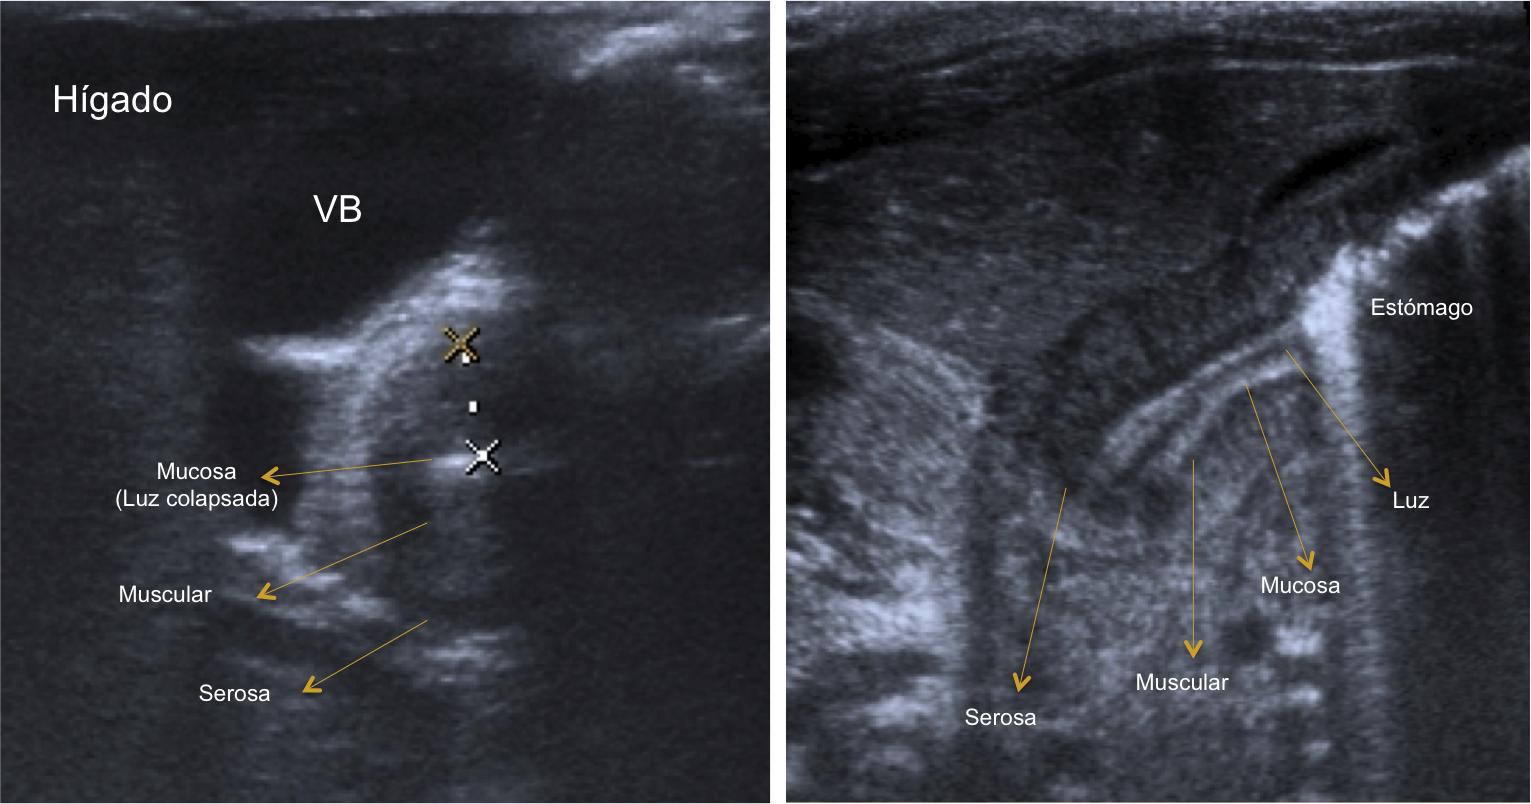

Las sondas que se deben utilizar son las lineales de entre 7-15 MHz (sondas de alta frecuencia). Estas sondas permiten identificar todas las capas de las pared del píloro. A la hora de realizar la prueba es mejor que el estómago se encuentre con poco contenido gástrico. Si el estómago esta lleno de gas se debe poner al paciente en posición oblicua anterior derecha, permitiendo que el líquido gástrico se deposite en el antro por efecto de la gravedad. Un truco es tratar de identificar en primer lugar la vesícula biliar, el píloro suele encontrarse adyacente a la misma.

El signo el doble rail se debe a que la mucosa comprimida presenta múltiples acúmulos líneales de líquido: se ven bandas de líquido hipoecogénicas con bandas hiperecogénicas tanto en visión longitudinal como transversal. En la sección transversal es típico observar la imagen en Donut o anillo hipoecoico heterogéneo con un centro hiperecogénico: el anillo hipoecogénico corresponde a la muscular engrosada, mientras que el centro hiperecogénico corresponder a la superficie mucosa redundante y edematosa.

Esquema axial y longitudinal.